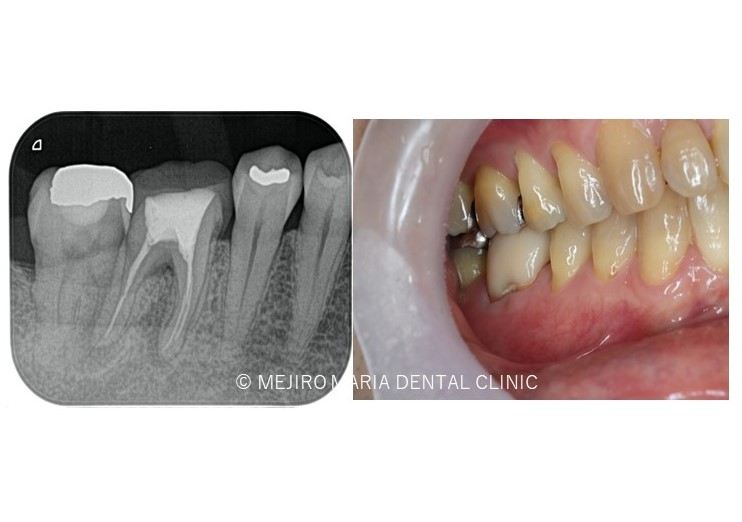

【症例】被せ物の下で進行した虫歯に対し精密根管治療で歯質を最大限に保存